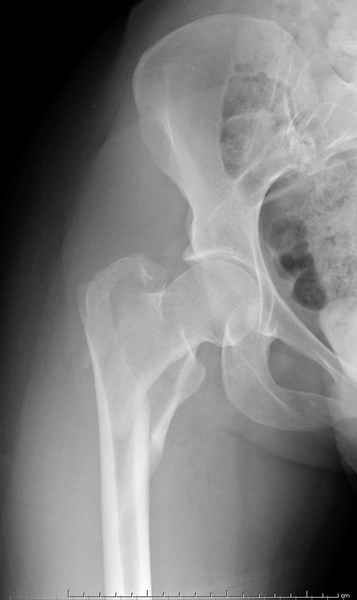

Уважаемые коллеги.Ко мне обратился мой коллега, весьма опытный травматолог, владеющий практически всеми видами остеосинтеза, с просьбой собрать мнения по поводу нескольких клинических случаев - два перелома бедра и перелом плеча.Если можно, подтвердите свое мнение иллюстрациями аналогичных ситуаций, либо ссылками - для клинического разбора. Бедро 1:Женщина 1929 г.р. Травма в результате падения 14.09.04г.Диагноз Закрытый оскольчатый чрезвертельный перелом правой бедренной кости со смещением отломков.Сопутствующие заболевания: ИБС, стенокардия напряжения, постинфарктный кардиосклероз (ИМ в 1992 году); гипертоническая болезнь 2 ст.; ожирение 3. Дополнительные данные - сохранная старушка.Спасибо.С уважением Александр Артемьев

Типичный остеопорозный вертельный перелом , не стабильный, 4-х фрагментный, базоцервикальный. Лечение оперативное не позднее 48 часов после перелома, чем раньше тем лучше, если общее состояние позволяет.

Фиксатор или DHS 130 градусов или PFN с короткой ножкой. Если DHS, то шуруп должен находиться в центре шейки и дополнительно еще простой длинный шуруп против ротации в проксимальной части шейки над шурупом DHS. Полную нагрузку на ногу начать через 6 недель.

Совершенно согласен с Mike, если у вас на очереди все представители компаний, предлагающие свои услуги, все методы хороши: пластины и шурупы, Compression Hip screw, Blade Plate, DCS, Intramedullary Nails:

Centromedullary and Cephalomedullary По классификация Seinsheimer

(1978) V- на основе количества фрагментов-нестабильный.

По Russel- Taylor Type II – Piriformis is not intact Type IIB – lesser

troch is not intact перелом с вовлечением двух кортексов и

вертела - нестабильный,

Деформирующие силы: В проксимальной части бедра

FAbER- Флексия, Абдукция, Наружная Ротация.

В Дистальном отделе Аддукторы ведут к Варусному положению.

Деформирующие силы усложняют закрытую репозицию и фиксацию Перед операцией КТ для определения степени вовлечения пириформис фосса.